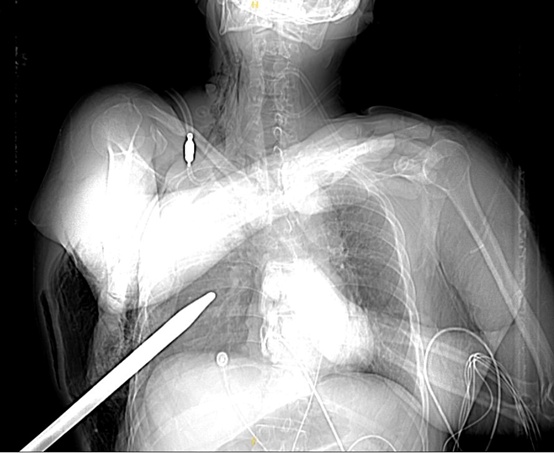

随行工友惊恐地描述了事故发生的瞬间,这名工人在作业过程中不慎从4米高空坠落,一根拇指粗的凿水泥錾子意外扎入他的胸腔。这一突如其来的事故让现场的人员都惊慌失措,他们迅速拨打120急救电话,并采取了简单的急救措施。

救护车到达恩泽医院急诊科后,医生立即对伤者进行初步检查及紧急处理,稳定生命体征。检查结果显示,伤者胸部受到严重损伤,出现张力性血气胸、失血性休克的状态,情况十分危急,需立即手术。

不幸中的万幸!未损伤心脏大血管

心胸外科副主任医师张波和主治医师金柯迅速联系麻醉科、重症监护室组成紧急手术团队,为伤者制定手术方案,实施胸腔镜探查手术。在微创胸腔镜技术下安全取出刺入胸腔的凿水泥錾子,切除右上肺叶以及部分中叶。据手术医生们介绍,凿水泥的錾子有15cm刺入胸腔,钢铁材质,贯穿右中肺叶和右上肺叶,胸腔内积血约2000ml,不幸的是上肺叶无法保留,幸运的是,患者衣服阻力阻止錾子的进一步深入,所幸并未损伤到心脏大血管,为抢救的成功创造了有利条件。